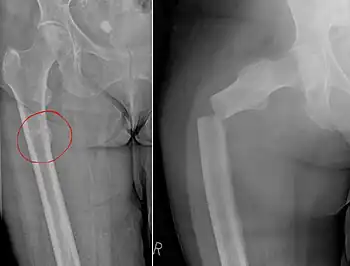

Chalkstick fracture

| Chalkstick fracture due to bone metastasis of breast cancer. Left image shows the metastasis, on the right a pathological fracture a few days later. | |

Chalkstick fractures are fractures, typically of long bones, in which the fracture is transverse to the long axis of the bone, like a broken stick of chalk.[1] A healthy long bone typically breaks like a hard woody stick as the collagen in the matrix adds remarkable flexibility to the mineral and the energy can run up and down the growth rings of bone. The bones of children will even follow a greenstick fracture pattern.

Chalkstick fractures are particularly common in Paget's disease of bone, and osteopetrosis.[2] It is also seen in cases of fused spine as in a patient with ankylosing spondylitis.[3]